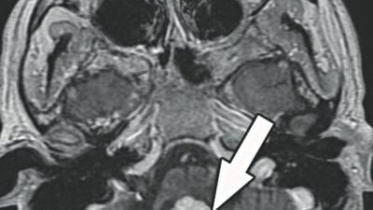

Apollo Hospitals Dhaka successfully operated a case of haemangioblastoma

A 33 year old Bangladeshi man was working abroad. He had a happy life. However, two months ago he started to have some problems.